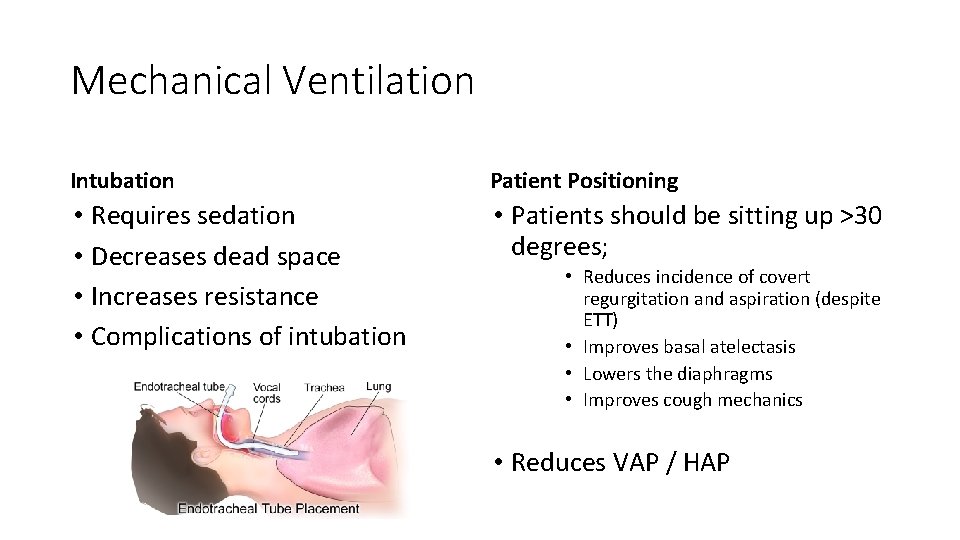

Mechanical Ventilation Intubation Patient Positioning • Requires sedation • Decreases dead space • Increases resistance • Complications of intubation • Patients should be sitting up >30 degrees; • Reduces incidence of covert regurgitation and aspiration (despite ETT) • Improves basal atelectasis • Lowers the diaphragms • Improves cough mechanics • Reduces VAP / HAP